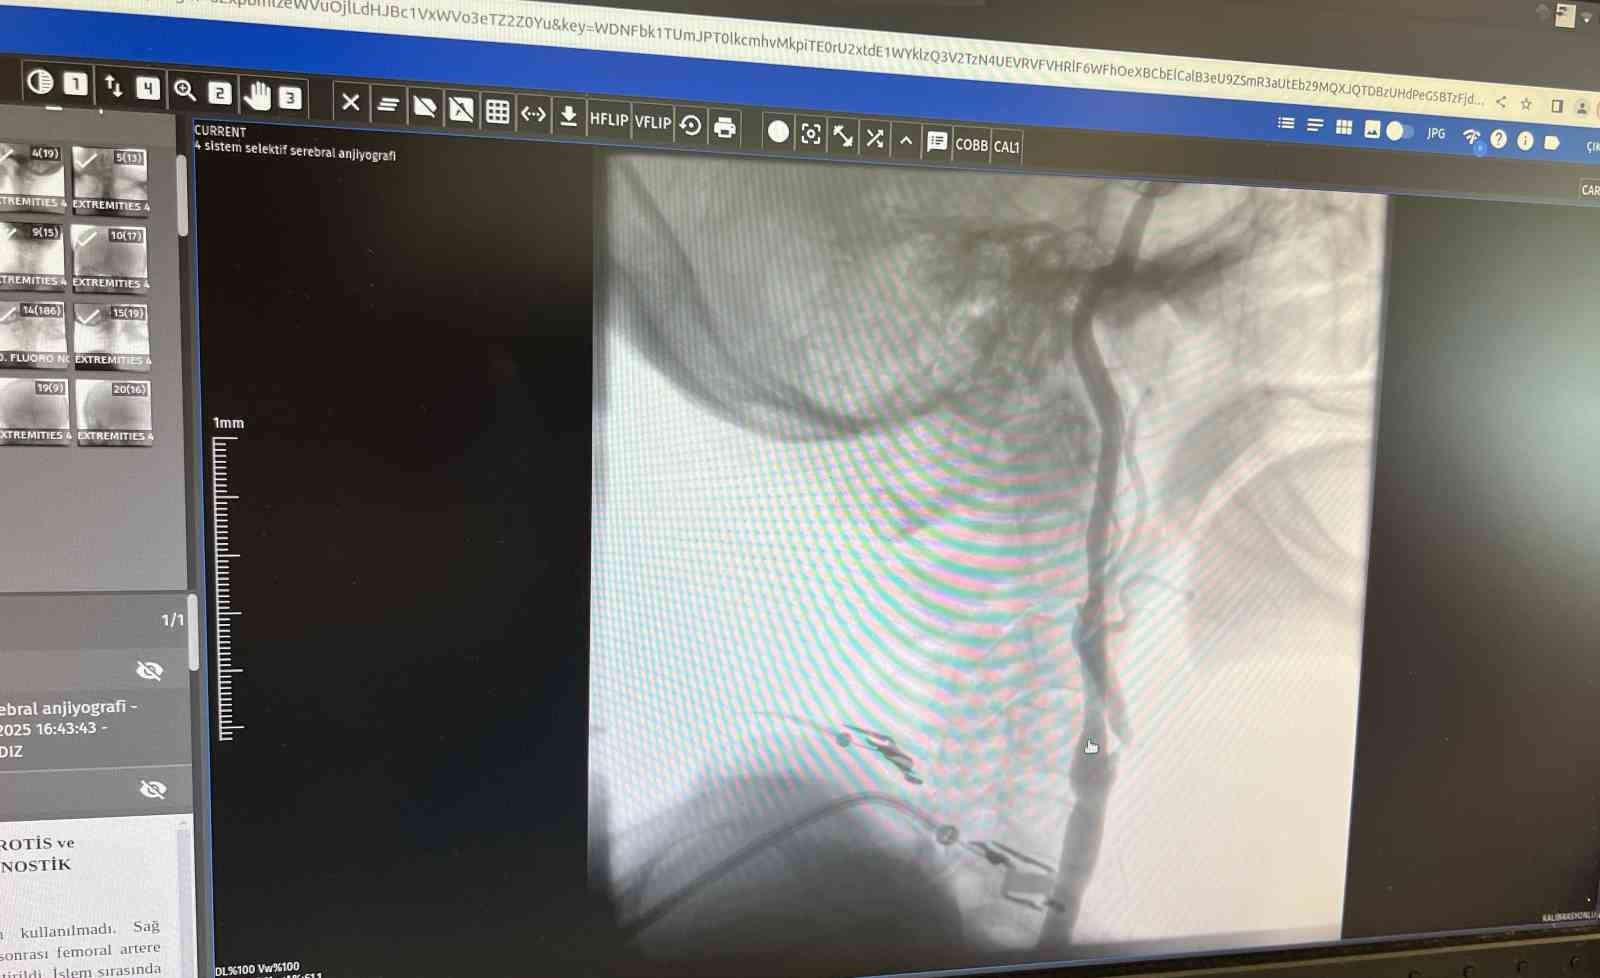

"Boyun damarlarını açma işlemi iki şekilde yapılabilir. Bir karotis endarterektomi dediğimiz ameliyatla bir diğer yöntem ise perkutan girişim dediğimiz stent yöntemiyle açılabilir. Biz kliniğimizde nöroloji ve kardiyoloji olarak bir konsey yapıyoruz. Damarı ciddi tıkalı olan ve buna bağlı felç geçirmiş hastalarda bu konseyde hastaya işlem yapıp yapmama kararı veriyoruz. Verdiğimiz karar çerçevesinde eğer hastaya işlem kararı vermişsek femoral arter dediğimiz kasık arterinden bir şitle 6 ya da 7 F çapında bir şitle ince bir boruyla bu damara giriş yapıyoruz ve boyun damarlarına ulaşıyoruz. Özellikle teller, filtreler ve stentlerle bu damarları açıp hastanın tedavisini gerçekleştiriyoruz. İşlem ameliyatsız olduğu için hastamız ertesi gün rahat bir şekilde problem olmazsa işlemde taburcu olabiliyor bu işlemden sonra. Bu işlemin yapılması için özellikle anjiografinin olduğu girişimsel nöroloji uzmanının ve girişimsel kardiyoloji uzmanının olduğu ve bu konuda yeterli vaka tecrübesine ve deneyime sahip uzmanların olduğu merkezler gerekir. Bunu yapabilmek için belli bir vaka sayısına ulaşmak ve bu konuda tecrübeli olmak gerekiyor. Biz de Manisa Şehir Hastanesi’ndeki girişimsel kardiyoloji ve nöroloji uzmanları olarak bu işlemi kliniğimizde efektif bir şekilde gerçekleştiriyoruz."